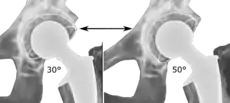

The direction of the acetabular cup influences the range of motion of the leg, and also affects the risk of dislocation.[7] For this purpose, the acetabular inclination and the acetabular anteversion are measurements of cup angulation in the coronal plane and the sagittal plane, respectively.